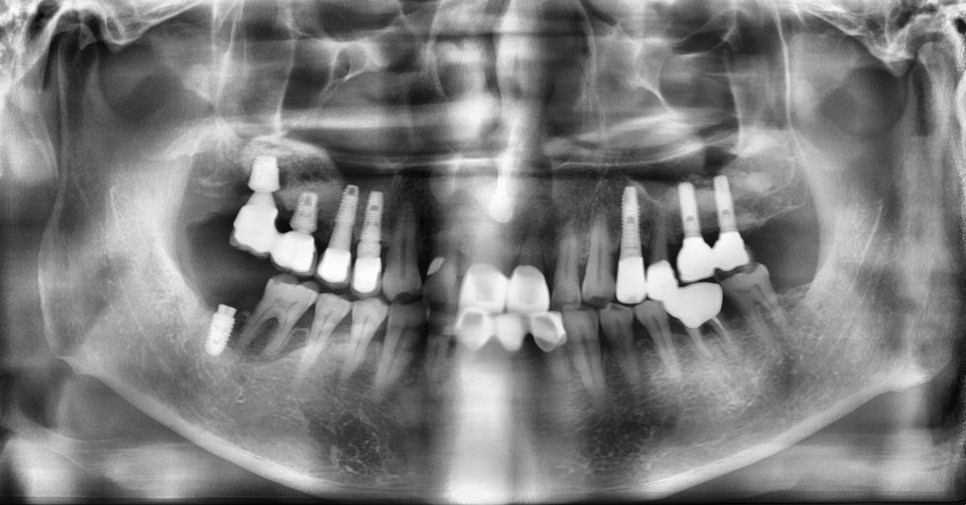

초진 X-ray (2025-1-23)

본 환자는 76세 남환으로 오른쪽 아래 어금니가 불편하여 내원하셨습니다. 문진시 당뇨병 병력이 있으셨으나, 평소 당화혈색소(HbA1c)가 6.5%로 비교적 잘 조절되고 있는 상태였습니다. 오른쪽 아래 어금니의 치근 파절로 진단되어 발치하기로 하였습니다. 마취 후 스트레스 또는 긴장으로 인하여 일시적으로 혈당이 급상승하였으나 10분 단위로 모니터링 하면서 200 이하로 혈당이 안정되는 것을 확인한 후 발치 시행하였습니다.